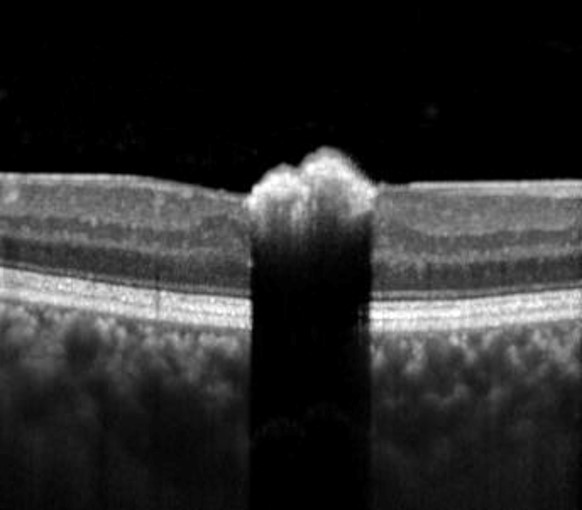

OCT imaging shows an elevated hyper-reflective lesion within the inner retina with deep posterior optical shadowing.

Spectralis OCT line scan through the lesion

Spectralis OCT volume scan through the lesion